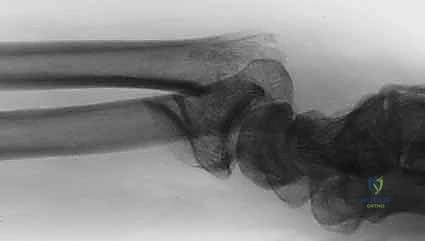

- الأشعة السينية (X-rays):

هي الخطوة الأولى لتقييم الكسر. يتم أخذ صور من زوايا متعددة (أمامية خلفية، جانبية، ومائلة) لتحديد موقع الكسر الأساسي ودرجة الانزياح والتقصير في عظم الكعبرة.

- التصوير المقطعي المحوسب (CT Scan) مع إعادة البناء ثلاثي الأبعاد:

هذا هو المعيار الذهبي الذي يعتمده الدكتور هطيف لجميع كسور المفصل المعقدة. تتيح الأشعة المقطعية رؤية كل شظية عظمية بوضوح تام، وتحديد حجمها، وموقعها، ودرجة تفتت السطح المفصلي بدقة ملليمترية. من خلال إعادة البناء ثلاثي الأبعاد (3D Reconstruction)، يمكن للدكتور هطيف "رؤية" الكسر من جميع الزوايا قبل فتح الجلد، مما يسمح له باختيار الغرسات (الصفائح والمسامير) الدقيقة لكل شظية وتحديد المداخل الجراحية المثلى.